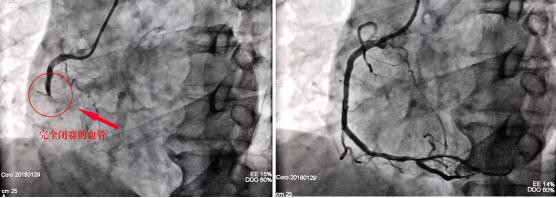

23时50分,老李经“绿色通道”绕行CCU冠心病重症监护病房由急诊科直接进入导管室,急诊PCI手术也随即就绪。此时,导管室急诊冠脉造影提示老李“心血管三支病变”,即前降支开口慢性完全性急性闭塞、回旋支重度狭窄、右冠近端急性闭塞。“诊断已经非常明确,立即行经皮微创冠脉介入治疗PCI开通闭塞的血管,这是挽救老李最快最有效的办法。”荆门二医胸痛中心技术总监、心血管内一科主任刘兵华内心十分清楚,这是唯一的机会,容不得半点迟疑。

00时20分,介入手术顺利完成,堵塞的血管被顺利打通。从进入导管室到堵塞的血管被打通仅仅用了30分钟。

冠脉造影下老李的血管从闭塞到开通